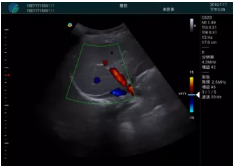

頸動(dòng)脈血流充盈飽滿(mǎn),無(wú)外溢

肝內血管顯示清晰,血流敏感無(wú)外溢

甲狀腺囊性結節,囊壁鈣化,透聲好

甲狀腺囊性占位